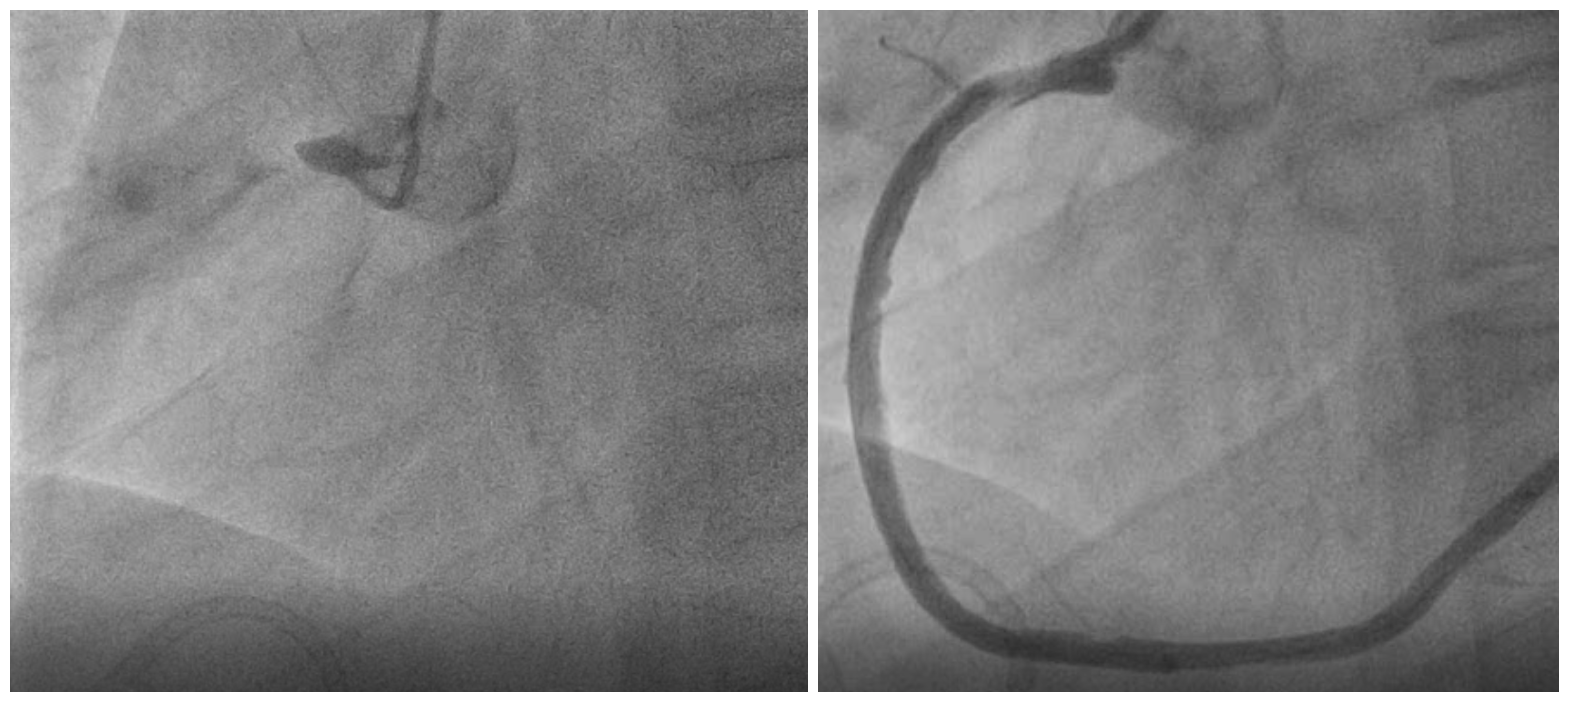

右冠脉完全闭塞、经过血栓抽吸后血流恢复

最终小何被收入急诊重症病房(EICU)进行综合管理治疗,介入血管外科为其实施了下腔静脉滤网植入+肝右动脉栓塞术,先期止血和解决下腔静脉血栓脱落问题,再由心内科实施冠脉内溶栓+抽血栓,确保其心脏血供,维持心肌功能,后期由李想副主任医师带领创伤小组进行围手术期的综合管理和治疗,解决抗凝与止血的平衡问题。